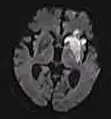

| Diffusion weighted (DWI) | Conventional | DWI | Measure of Brownian motion of water molecules.[78] | High signal within minutes of cerebral infarction (pictured).[79] | ![]() |